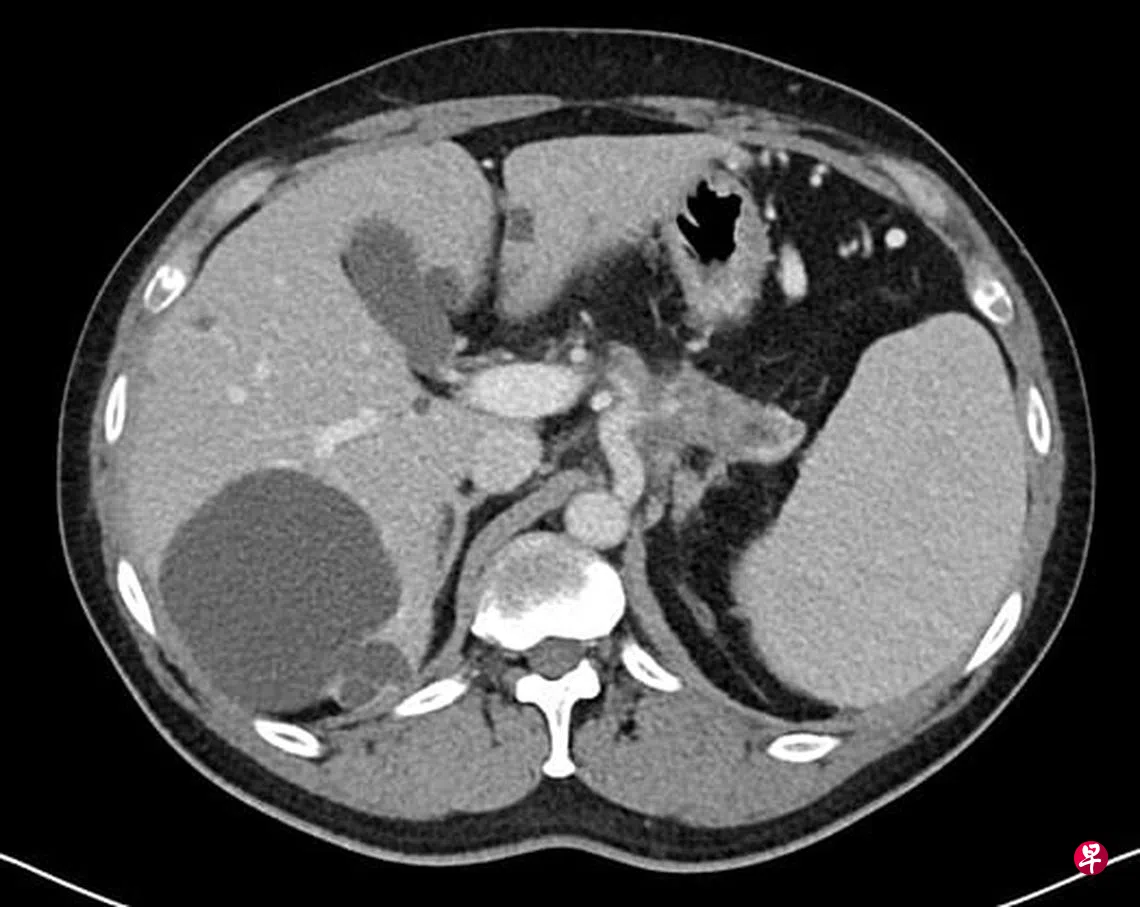

在新加坡,胰腺癌的死亡率,男女排名为第五。胰腺癌是目前较为难以治愈的癌症,归咎于不同原因:其一、胰腺的所在位置是腹腔最为深入的部位,是胃脏的后面,在大动脉及脊髓的前面。如肿瘤长在胰腺头部,病人有可能因黄疸迹象(如尿液呈茶色、皮肤发黄、眼白发黄或粪便呈灰色等)而寻医。但是,若肿瘤长在胰腺体部及尾部,发现时大多都太迟了。由于所在位置非常深入,而且早期没有症状,肿瘤必须长到一定的程度,开始侵袭周边组织,方造成症状。所以,大多的胰腺癌当发现时已经晚了。